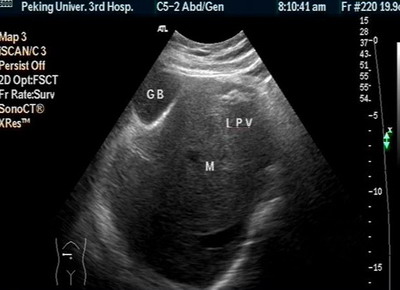

肝脏B超:右肝内及肝尾叶可见巨大强回声结节,9.3×8.8cm,边界欠清,后方回声增强。CDI:肿物周边可见肝动静脉绕行及肿物内门静脉穿行,无明显压迫现象。脾厚5.0cm肋下3.2cm脾门处脾静脉宽0.8cm